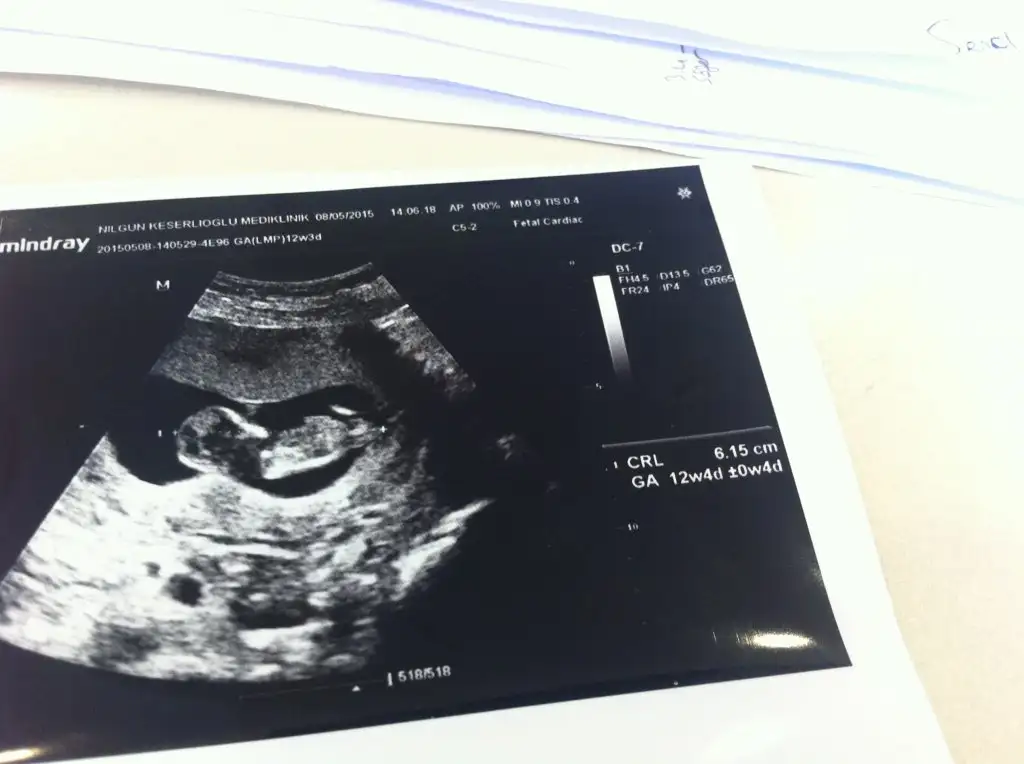

bu da 12+3 haftalık son halimiz arkadaşlar...